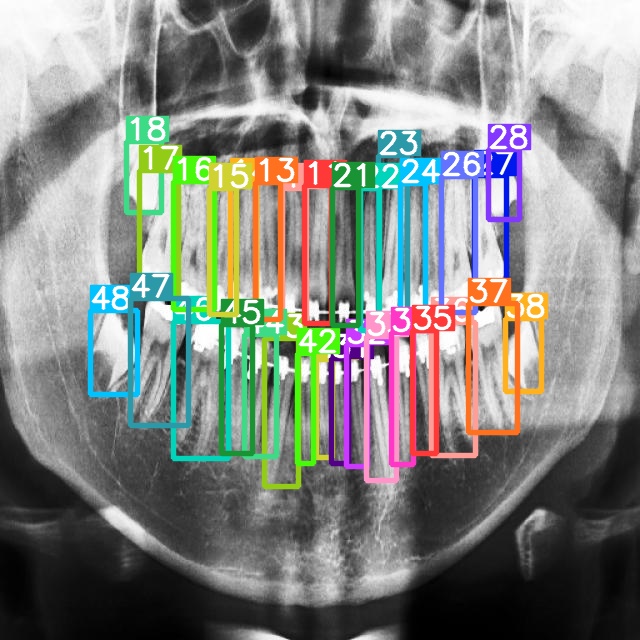

The FDI World Dental Federation notation [5] shown in Fig.1 is a dental notation system used to identify and label teeth uniquely. It is a standard method used worldwide to communicate tooth information in a consistent and universally understood way. The FDI notation system assigns a two-digit number to each tooth in the mouth and is widely used by dental professionals.

Refer to caption

Figure 1: FDI Teeth Numbering Notation